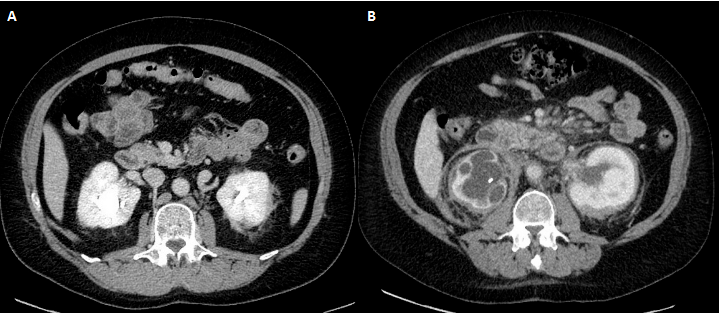

[ 另一位ECD患者 ]

图A:示肾周边疆不清的线状软组织影(“毛肾征”),双侧轻度肾积水

图B:随访9年后,肾周和肾门周围软组织浸润(“毛肾征”),病变较前明显停顿。